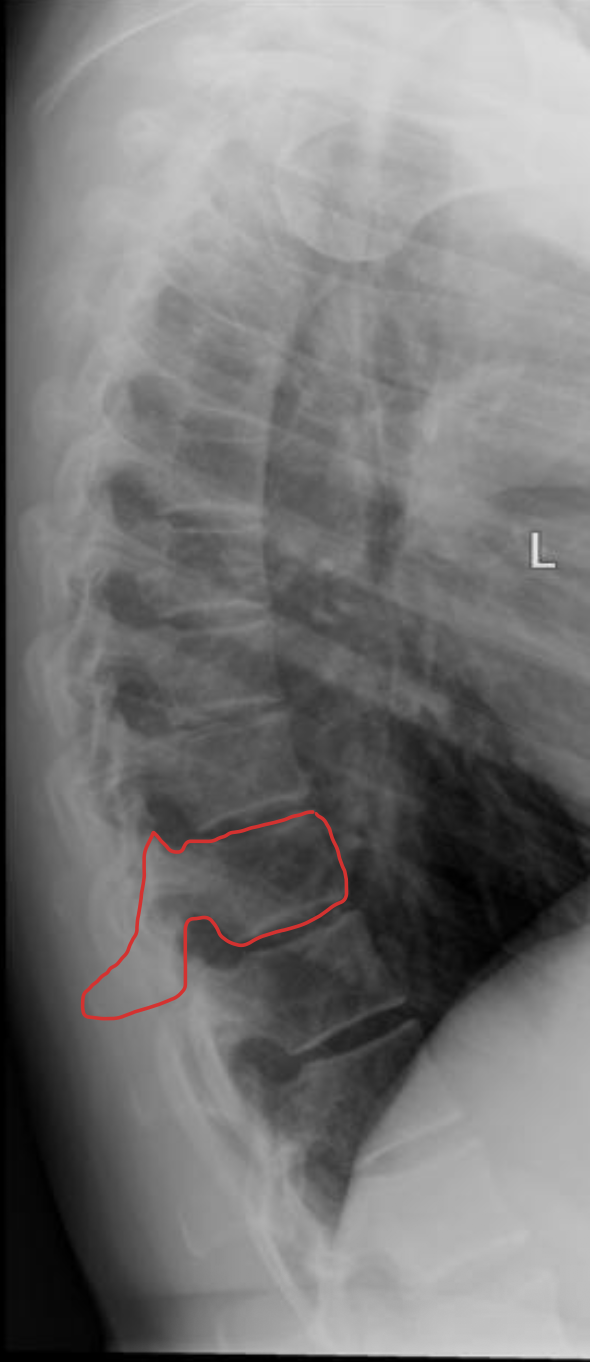

腰椎 5 块

Lumbar vertebrae

腰椎

LUMBAR

椎间盘

Intervertebral disc

关节突关节(小关节)

Zygapophyseal